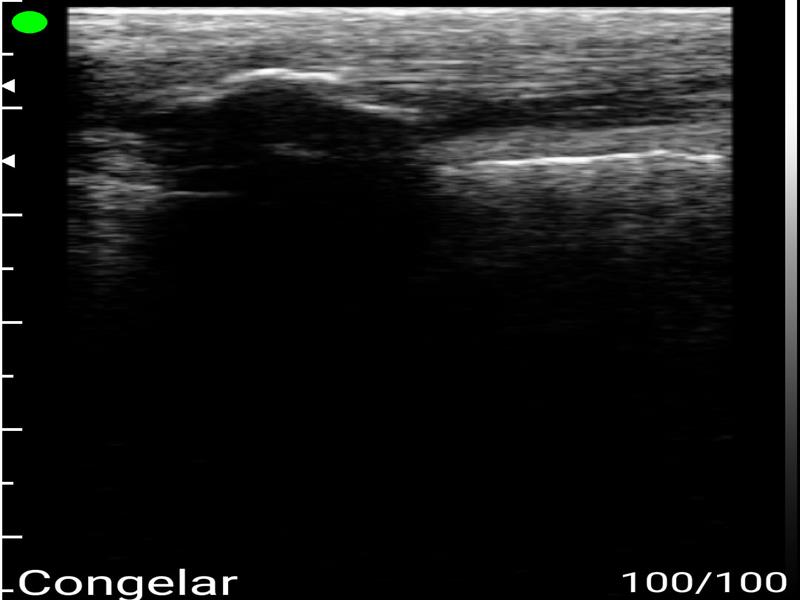

Ecografía Muscular o Tendinosa Clínica FisioPatraix

Es una prueba que se realiza mediante ultrasonidos y que consiste en ver una parte del cuerpo determinada en tiempo real. Con este examen se pueden ver lesiones en:

Es indolora y ayuda a detectar posibles problemas del paciente en hombros, codos, muñecas, rodillas, tobillos… etc. Los exámenes por ultrasonido son rápidos y fácilmente tolerables por la mayoría de los pacientes.